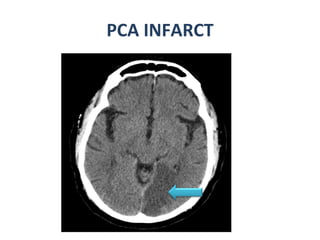

PCA INFARCT

Cerebral Arterial Territory MCA -most of  lateral hemisphere ,  Basal ganglia, insula,  ACA- Inferomedial basal ganglia,ventromedial frontal lobes,  anterior 2/3rd medial cerebral hemispheres , 1 cm supero medial brain convexity PCA -Thalami, midbrain,  posterior 1/3of medial hemisphere , occipital lobe,  postero medial temporal lobe